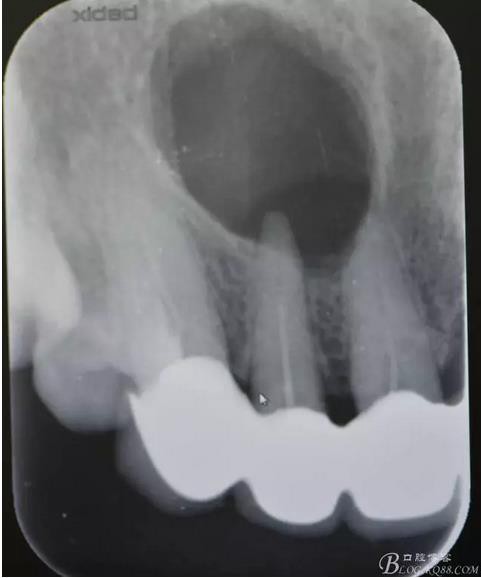

圖1.術前的根尖片影像檢查:11、12根管治療不完善